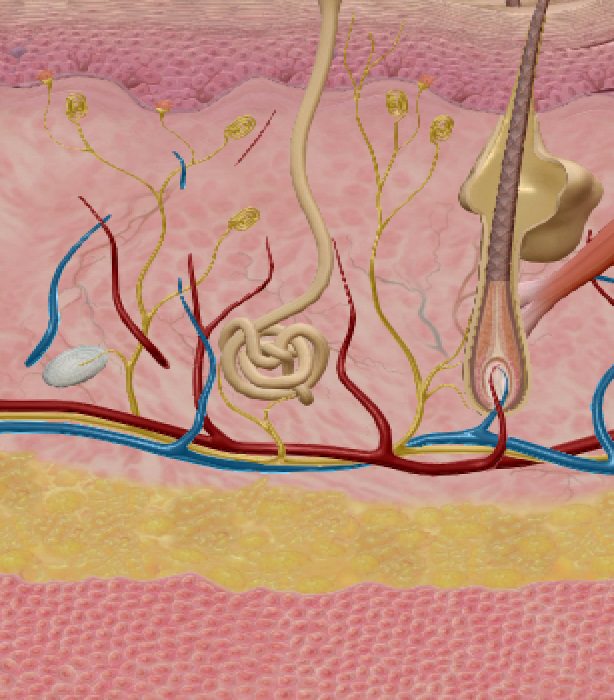

SISTEM INTEGUMENTARI

KULIT adalah organ yang terbesar pada tubuh manusia yang berperanan antara lain menjadi batas pelindung organ-organ dalaman dari terdedah pada mikro organisma dari persekitaran luar.

Kulit juga merupakan satu agen ‘sensori’ dimana apa jua yang berlaku keatasnya akan dapat dirasakan melaui jaringan sensori dan saraf yang memberi isyarat kepada otak untuk tindakan selanjutnya.

Apakah bicara ALQuran tentang kulit? Firman Allah pada ayat 56 surah An-Nisa’ memberitahu bahawa reseptor deria rasa sakit pastinya terdapat pada kulit yang menjurus kepada cabang anatomi yang disebut sistem Integumentari.

Pada ayat 23 surah Az-Zumar dikhabarkan bahawa adanya semacam deria rasa pada kulit ketika wujudnya rasa ketakutan atau keresahan sepertimana kita kadangkala menyebut “berdiri bulu roma”. Kadangkala kita merasakan seperti ada rasa tusukan pada kulit dan juga rasa seperti ada semut bergerak dipermukaan kulit. Demikianlah beberapa sifat kulit yang bertukar mengikut kewujudan sensori yang menyentuh perasaan atau saraf. Sentuhan pada kulit juga dapat merangsang saraf selari dengan cara sentuhan dilakukan.

Kulit juga dikhabarkan mempunyai kuasa menyimpan memori data yang akan dikeluarkan kembali pada Hari Kiamat nanti seperti mana difirmankan pada ayat 19-21 surah Fussilat.

Tiga potong ayat ini memberi bayangan bahawa kulit yang menjadi pelindung tubuh kita akan menjadi saksi diHari Kiamat nanti. Sekiranya kita mendalami ilmu DNA dan kaitannya pada kulit kita akan sedikit sebanyak mendapat pencerahan.

Pada pertengahan tahun 2007 majalah “Neuroscience” telah menerbitkan satu kajian saitifik terhadap kulit dimana mereka mendapati wujudnya sel yang mengandungi molekul CaMKII yang bertanggungjawab dalam menyimpan ‘memori’.